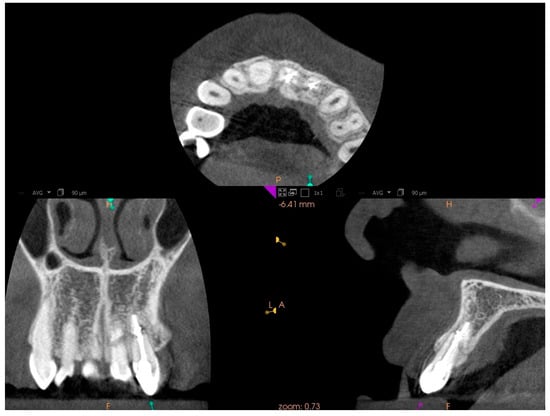

In tooth 21, we successfully performed the root canal treatment with minimal loss of tooth tissue, covering both fragments of the fractured tooth root. The aim of the study is to assess whether the treatment of tooth 22 with root canal obliteration using endodontic navigation will bring positive clinical and radiological effects. The use of the endodontic template will be evaluated through clinical and radiological assessments of the tooth before the initiation of endodontic treatment and after the completion of the treatment. After obtaining both written and verbal consent to perform the endodontic procedure, an endodontic template was designed. The patient presented for root canal treatment of tooth 22. During the initial visit, a CBCT (Carestream 9300C, Carestream Dental, 2016, Atlanta, GA, USA) of the maxillary arch was completed (Figure 3a), and an intraoral scan (Carestream 3600) of the jaw was performed.

Figure 3. CBCT images presenting tooth no. 22: (a) before treatment, (b) after treatment.

This software allowed for the preparation of the file for 3D printing by adding supports and slicing the template into layers of 50 µm thickness. The template was then printed using dedicated transparent resin—Class IIa (NextDent SG, Istanbul, Turkey) on a 3D printer (Phrozen Sonic Mini 4K, Taipei, Taiwan) [18,19]. The post-processing phase was conducted in strict conformity with the resin manufacturer’s instructions to prevent dimensional alterations [20]. The placement of the template in the oral cavity was checked, and the treatment area was isolated. The patient was locally anesthetized with infiltration using Dentocaine (1 ampoule, Inibsa, Madrid, Spain). The temporary filling was removed from tooth 22. The template was placed on the upper arch, and canal access was initiated using a Munce bur #1 (Munce Discovery BurTM). The template was removed after the bur reached a depth 2 mm greater than previously planned, to irrigate the root canal with a 5.25% NaOCl solution, allowing for endodontic access control and cleaning of the Munce bur. The work continued until the bur achieved the planned length previously set. The position of the canal was checked using C-pilots (VDV, Munich, Germany) ISO 10 and ISO 15. Following that, RVG was performed (Figure 2b) to confirm the correct position of the instrument in the canal and the length of the canal. The canal was prepared using Reciproc Blue (VDV, Munich, Germany) endodontic instruments to the working length, confirmed by measurements with an endometer (Raypex 5, VDW, Munich, Germany) and radiographically. The canal was irrigated using protocol along with ultrasonic activation (PUI) with 5.25% NaOCl, 40% citric acid, and triple-distilled water. After drying the root canal with a paper point (Reciproc 25, VDV), the canal was filled with gutta-percha by a Continous Wave Obturation (CWO) (Reciproc 25, VDV, and BeeFill 2in1 Obturation Kit, VDW GmBH, Munchen, Germany) with the sealer AH Plus (Dentsply DeTrey GmbH, Philadelphia, PA, USA). After filling the canal, RVG (Figure 2c) and CBCT imaging (Figure 3b) were performed to verify the accuracy of the canal filling. Finally, a permanent composite filling (Gradia Direct, GC, Tokyo, Japan) was placed. The patient returned for follow-up visits at 3 and 6 months, reporting a complete resolution of pain. Clinically, there was no pain upon vertical percussion, and there was no tenderness upon palpation of the alveolar process. The buccal mucosa presented without clinical changes. The mobility of the tooth was within the physiological limits (Grade 1 Miller mobility index) [15]. Radiographically, there were no signs of external resorption or inflammation around the tooth fragments and there were no periapical changes observed. The patient was advised to continue with regular follow-ups. At the 12-month follow-up visit, the patient exhibited no deviations from normal clinical findings. The examination revealed consistent results with the previous visit, showing no signs of discomfort, tenderness, or radiographic abnormalities (Figure 6 and Figure 7). The patient was informed about the need for further regular check-ups and to urgently report for a visit in case of any disturbing symptoms, such as recurrent pain, increased tooth mobility, or swelling.

Figure 6. CBCT images presenting tooth no. 22 after 12 months of treatment.